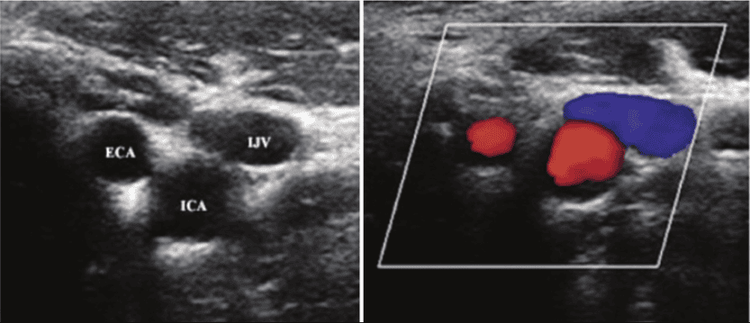

• Siêu âm động mạch cảnh (bao gồm siêu âm Doppler): Kỹ thuật này sử dụng sóng âm thanh để tạo ra hình ảnh thời gian thực của các động mạch và xác định vị trí tắc nghẽn. Doppler là kỹ thuật siêu âm đặc biệt có thể phát hiện các khu vực lưu lượng máu bị giảm trong động mạch.

Siêu âm Doppler giúp chẩn đoán bệnh động mạch cảnh